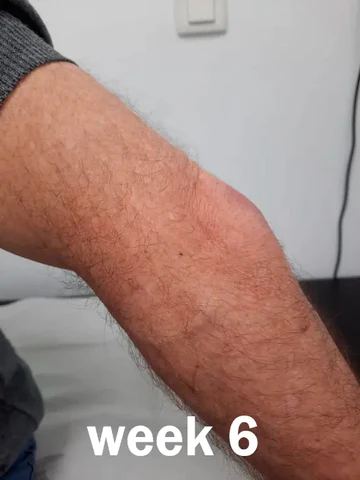

WILLIAM USED PERFECTX™ JOINT & BONE THERAPY CREAM FOR SIX WEEKS TO SUCCESSFULLY TREAT OLECRANON BURSITIS.

My elbow joint had been aching for some time, and I barely noticed it until it started to swell and the pain became unbearable. After consulting my doctor, I learned that I had olecranon bursitis. I tried various treatments and therapies, but unfortunately none of them had any lasting effect. I was feeling very discouraged and hopeless, until I discovered Perfectx™ Joint & Bone Therapy Cream online. In the first week of use, I felt its magic – the white cream quickly penetrated my skin after application and I felt my pain gradually reduce. I was amazed by the results! I have full confidence in this product and will continue to use it.

“I have been using Perfectx™ Joint & Bone Therapy Cream for 3 weeks now, and I make sure to apply it religiously day and night. I’m delighted to report that the pain has almost completely gone away and the swelling caused by bone inflammation has been dramatically reduced. I’m sure that with a few more weeks of using this remarkable product, my arm will be back to its former glory.”

I’ve been using Perfectx™ Joint & Bone Therapy Cream for the past 6 weeks, and I can honestly say that it has completely cured my Olecranon burstitis. Not only do I feel more flexible, but I can also lift heavy things without any pain or discomfort. It’s been a real lifesaver, both in terms of money and time I would’ve spent in pain. I’m not exaggerating when I say that it’s really been like having an orthopedic specialist in a bottle! I’m now determined to spread the word about this amazing product to other people suffering from bone diseases.”